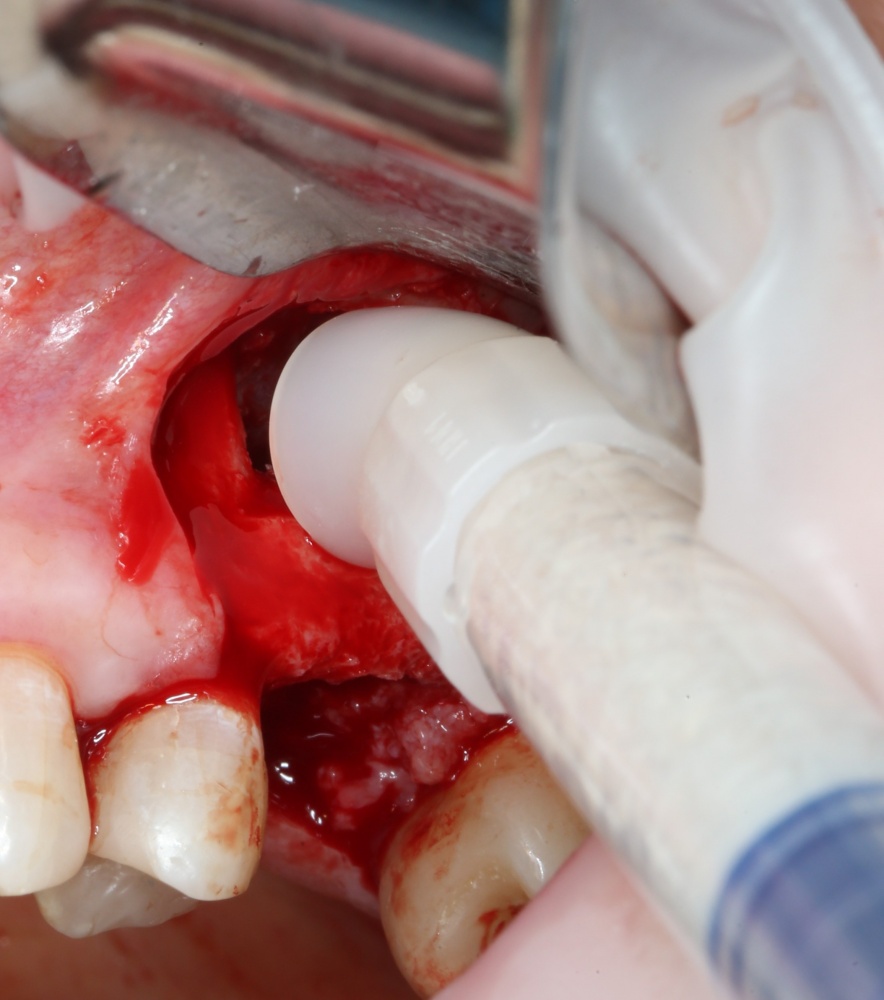

Для получения костного блока, мы открываем донорскую зону, наружную косую линию нижней челюсти.

Получение костного аутотрансплантата.

Здесь потребуется пародонтологический зонд с миллиметровой разметкой или какой-то другой измерительный прибор (операционная линейка). Ранее по КЛКТ я измерил костный дефект, теперь нужно нанести границы будущего костного блока на донорскую зону.

Ремарка: некоторые доктора предлагают делать хирургические шаблоны или выкройки специально для точного забора костного блока. На мой взгляд, это чрезмерное усложнение - во-первых, использование подобных шаблонов или выкроек требует увеличения площади раны, во-вторых, это увеличивает время и стоимость лечения, в-третьих, на этом этапе не требуется высокая точность, поскольку блок всё равно потребует адаптации.

Иными словами, важна не точность, а быстрый, аккуратный и, что главное, малотравматичный забор аутотрансплантата.

Для получения костного блока мы использовали ультразвуковую пьезохирургическую систему. Это самый удобный и безопасный инструмент для проведения подобных манипуляций. С помощью него мы сформировали и выделили костный блок. Он должен отделяться легким движением остеотома или элеватора. Как это сделать правильно — читай здесь>>

Кстати, если костный блок не отделяется от костного ложа легким движением элеватора, значит он неправильно сформирован или не до конца выделен. Вообще, любое чрезмерное усилие в хирургии — это всегда следствие рукожопия. Если тебе что-то приходится делать с усилием (установка имплантата, удаление зуба и т. д.) — значит ты делаешь это неправильно. Остановись и подумай, что именно.